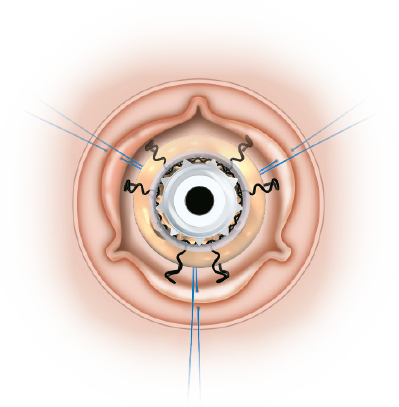

Clear visibility

The Nitinol stent provides clear visibility under fluoroscopy and CT scan to identify landmarks which facilitate the ViV procedure.

Even circumferential expansion

The inflow ring can be evenly and circumferentially expanded up to 2.5mm above its nominal size, which allows for hemodynamic advantages and greater compatibility with TAVI models and sizes.